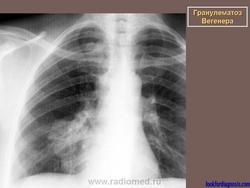

Поражение легкихразвивается у 3/4 больных, проявляется формированием инфильтратов, которые могут распадаться и образовывать полости. Иногда наблюдается плеврит.

При генерализованной форме ........ картина пневмонии с наклонностью к абсцедированию и появлению плеврального выпота.

Рентгенологическое исследование легких: инфильтраты, часто с распадом и образованием полостей, редко - плеврит.